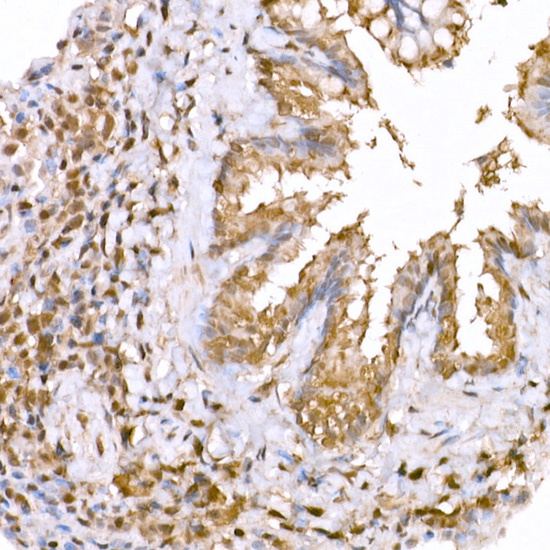

Immunohistochemistry analysis of paraffin-embedded Human colon using AMPKa1/AMPKa2 Rabbit pAb (CAB12718) at dilution of 1:20 (40x lens). High pressure antigen retrieval performed with 0.01M Citrate buffer (pH 6.0) prior to IHC staining.